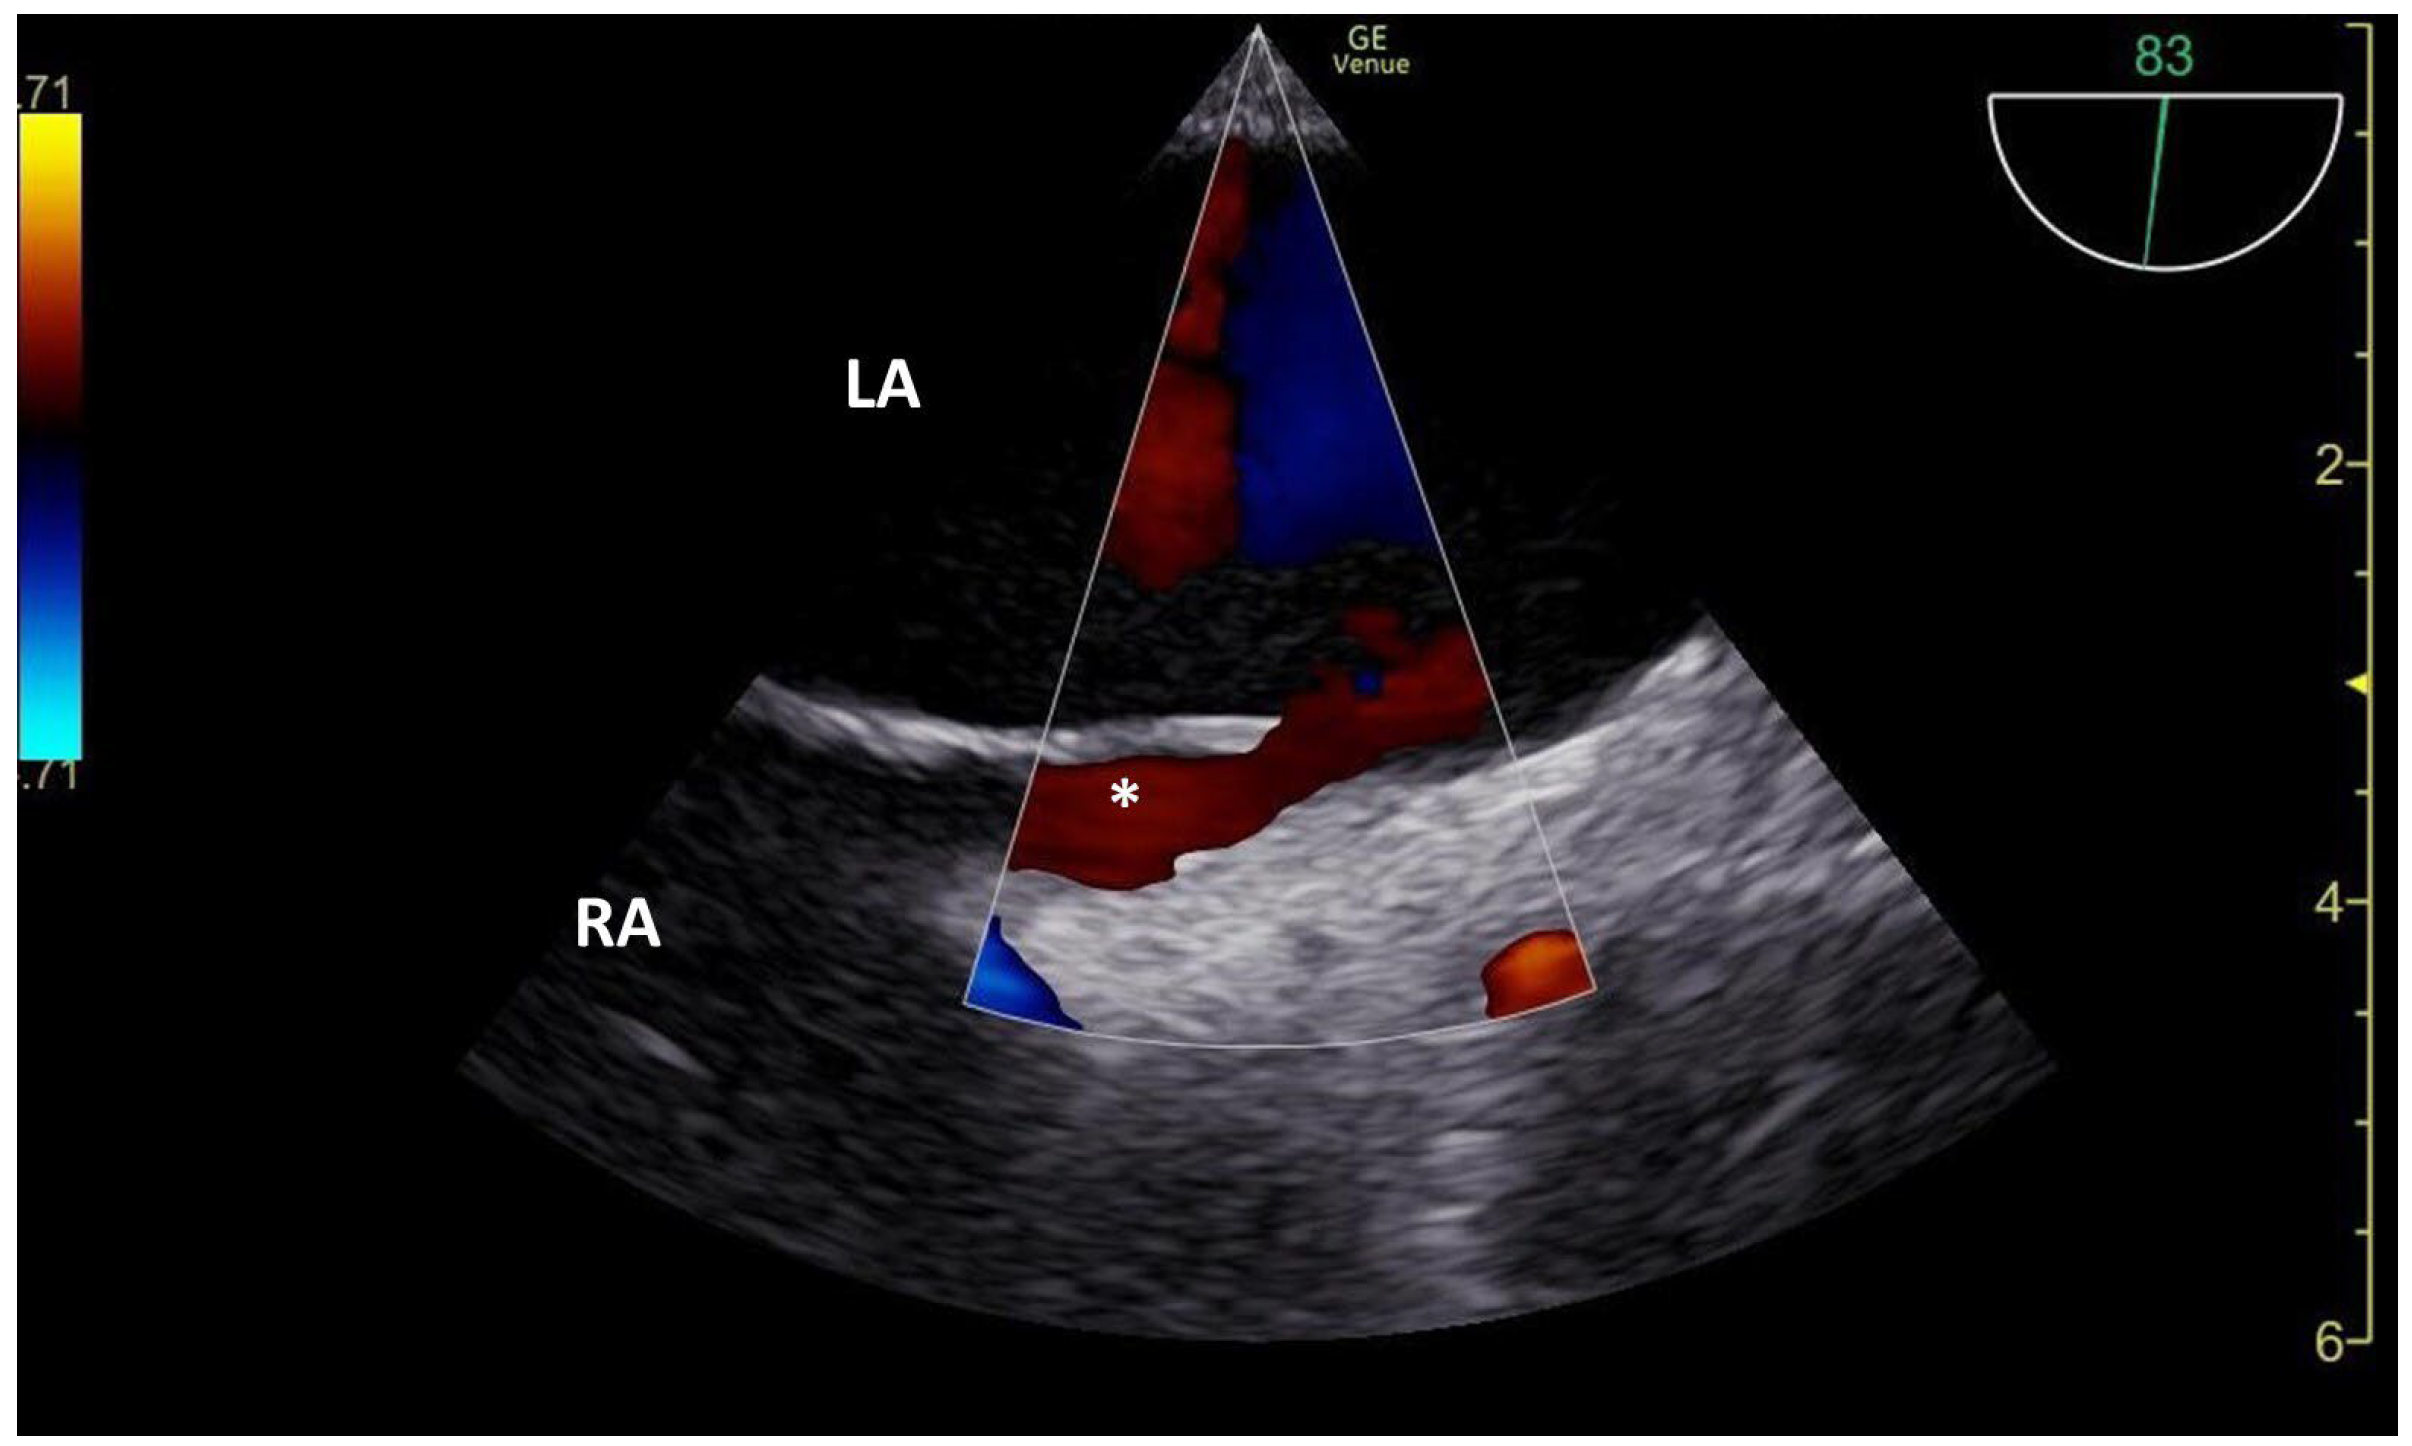

3.1. TCCD MES-Positive Case 1

3.2. TCCD MES-Positive Case 2

3.3. TCCD MES-Positive Case 3